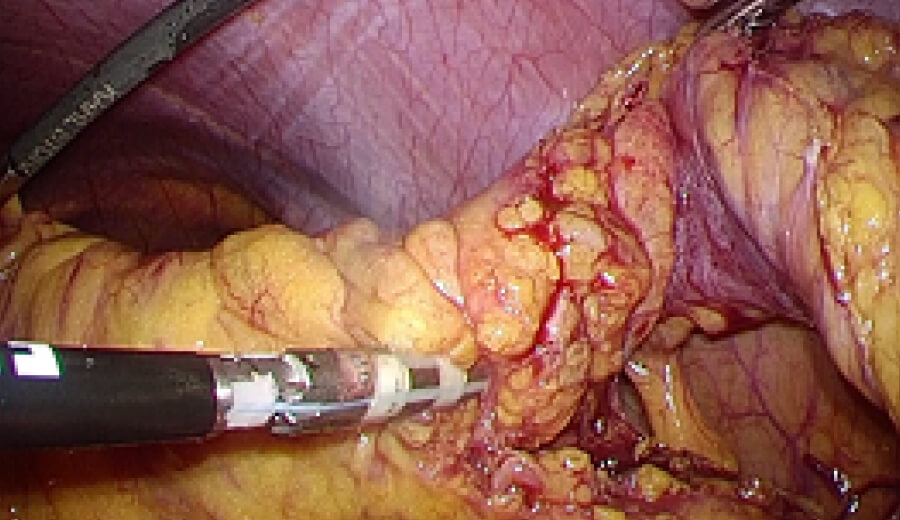

図2 潰瘍性大腸炎に対する腹腔鏡下大腸全摘術